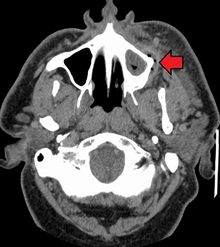

Diagnostic approach

A periodontal abscess may be difficult to distinguish from a periapical abscess. Indeed, sometimes they can occur together.[2] Since the management of a periodontal abscess is different from that of a periapical abscess, this differentiation is important to make.

- If the swelling is over the area of the root apex, it is more likely to be a periapical abscess; if it is closer to the gingival margin, it is more likely to be a periodontal abscess.

- Similarly, in a periodontal abscess pus most likely discharges via the periodontal pocket, whereas a periapical abscess generally drains via a parulis nearer to the apex of the involved tooth.[2]

- If the tooth has pre-existing periodontal disease, with pockets and loss of alveolar bone height, it is more likely to be a periodontal abscess; whereas if the tooth has relatively healthy periodontal condition, it is more likely to be a periapical abscess.

- In periodontal abscesses, the swelling usually precedes the pain, and in periapical abscesses, the pain usually precedes the swelling.[2]

- A history of toothache with sensitivity to hot and cold suggests previous pulpitis, and indicates that a periapical abscess is more likely.

- If the tooth which gives normal results on pulp sensibility testing, is free of dental caries and has no large restorations; it is more likely to be a periodontal abscess.

- A dental radiograph is of little help in the early stages of a dental abscess, but later usually the position of the abscess, and hence indication of endodontal/periodontal etiology can be determined. If there is a sinus, a gutta percha point is sometimes inserted before the x-ray in the hope that it will point to the origin of the infection.

- Generally, periodontal abscesses will be more tender to lateral percussion than to vertical, and periapical abscesses will be more tender to apical percussion.[2]